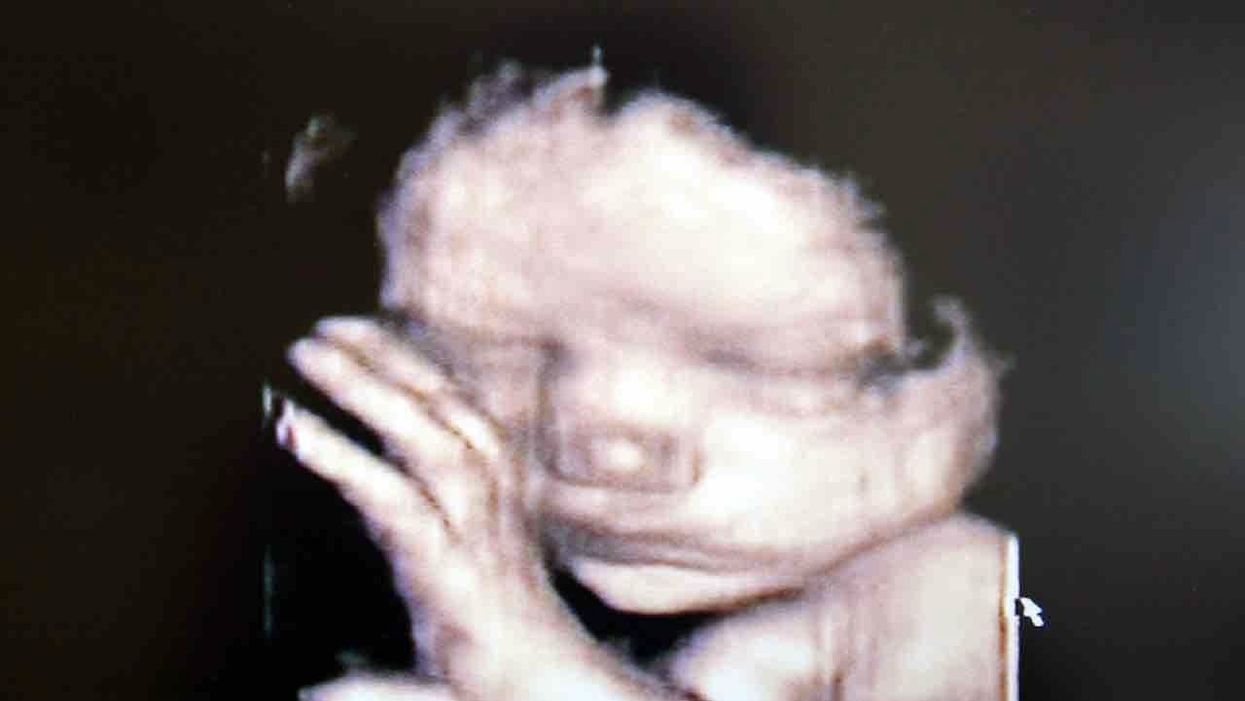

Here is a 4D ultrasound video of a baby in the womb. The clip's description says the baby is 34 weeks old — the same age of the infant in the aforementioned court case:

4D Ultrasound of 34 Week Babyyoutu.be